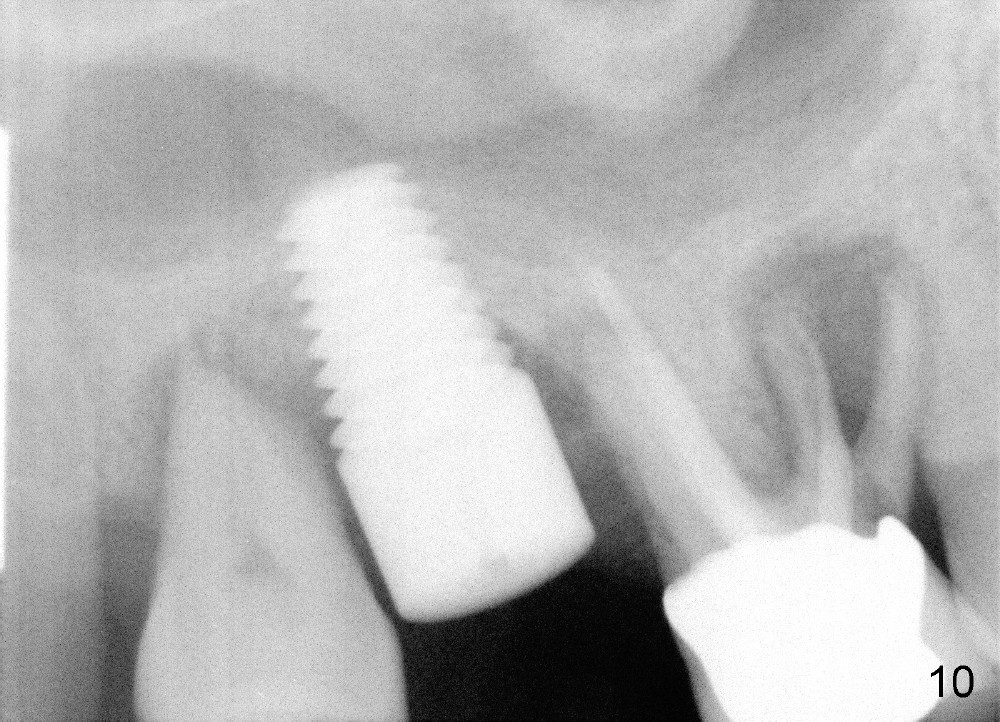

Six months post cementation, the patient returns for follow-up (Fig.11-14) with chief complaint of food impaction between the upper right last 2 teeth. It is difficult to remove. The distal 2nd thread appears not to be covered by the bone, whereas the mesial one is (compare Fig.11 arrowheads). The buccal gingiva is apparently within normal limit (Fig.12) except the distal (Fig.13 >). The distolingual gingiva recession is much more severe (Fig.14). There are deep pockets with tenderness in the abnormal sites. The tooth #1 has #2 mobility with tenderness. The patient agrees to have it extracted and restored with an implant, since the tooth #32 is functional. Bone graft will be placed in the lingual aspect of the implant at the site of #2.